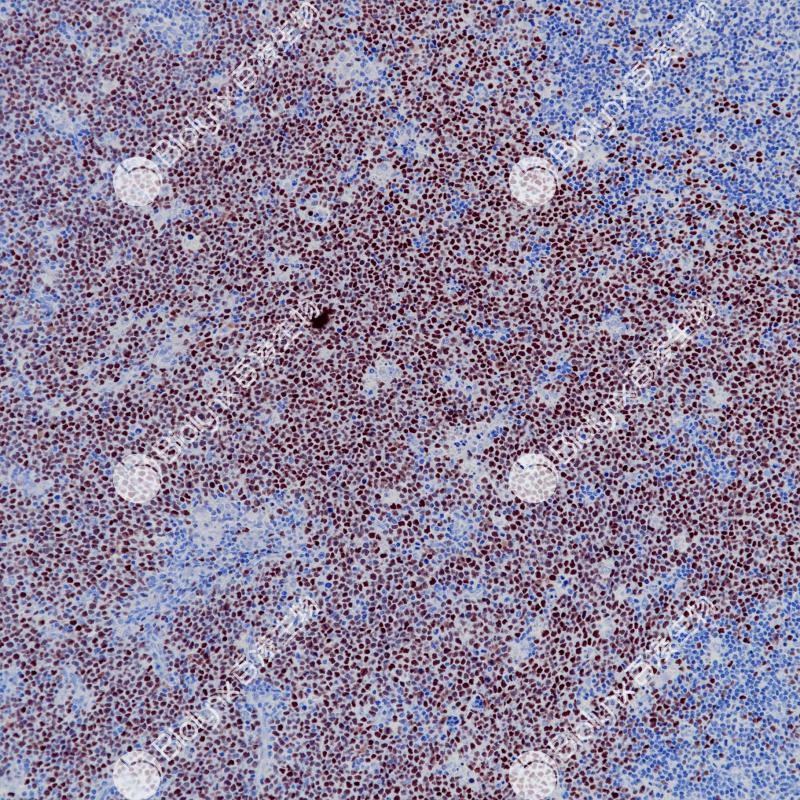

IgM是B淋巴细胞表面主要的免疫球蛋白之一,该抗体可以与免疫球蛋白IgM的μ链反应,对一些淋巴瘤的鉴别诊断具有一定的辅助意义,也可用于对肾小球肾炎进行功能性分类。

阳性对照

扁桃体